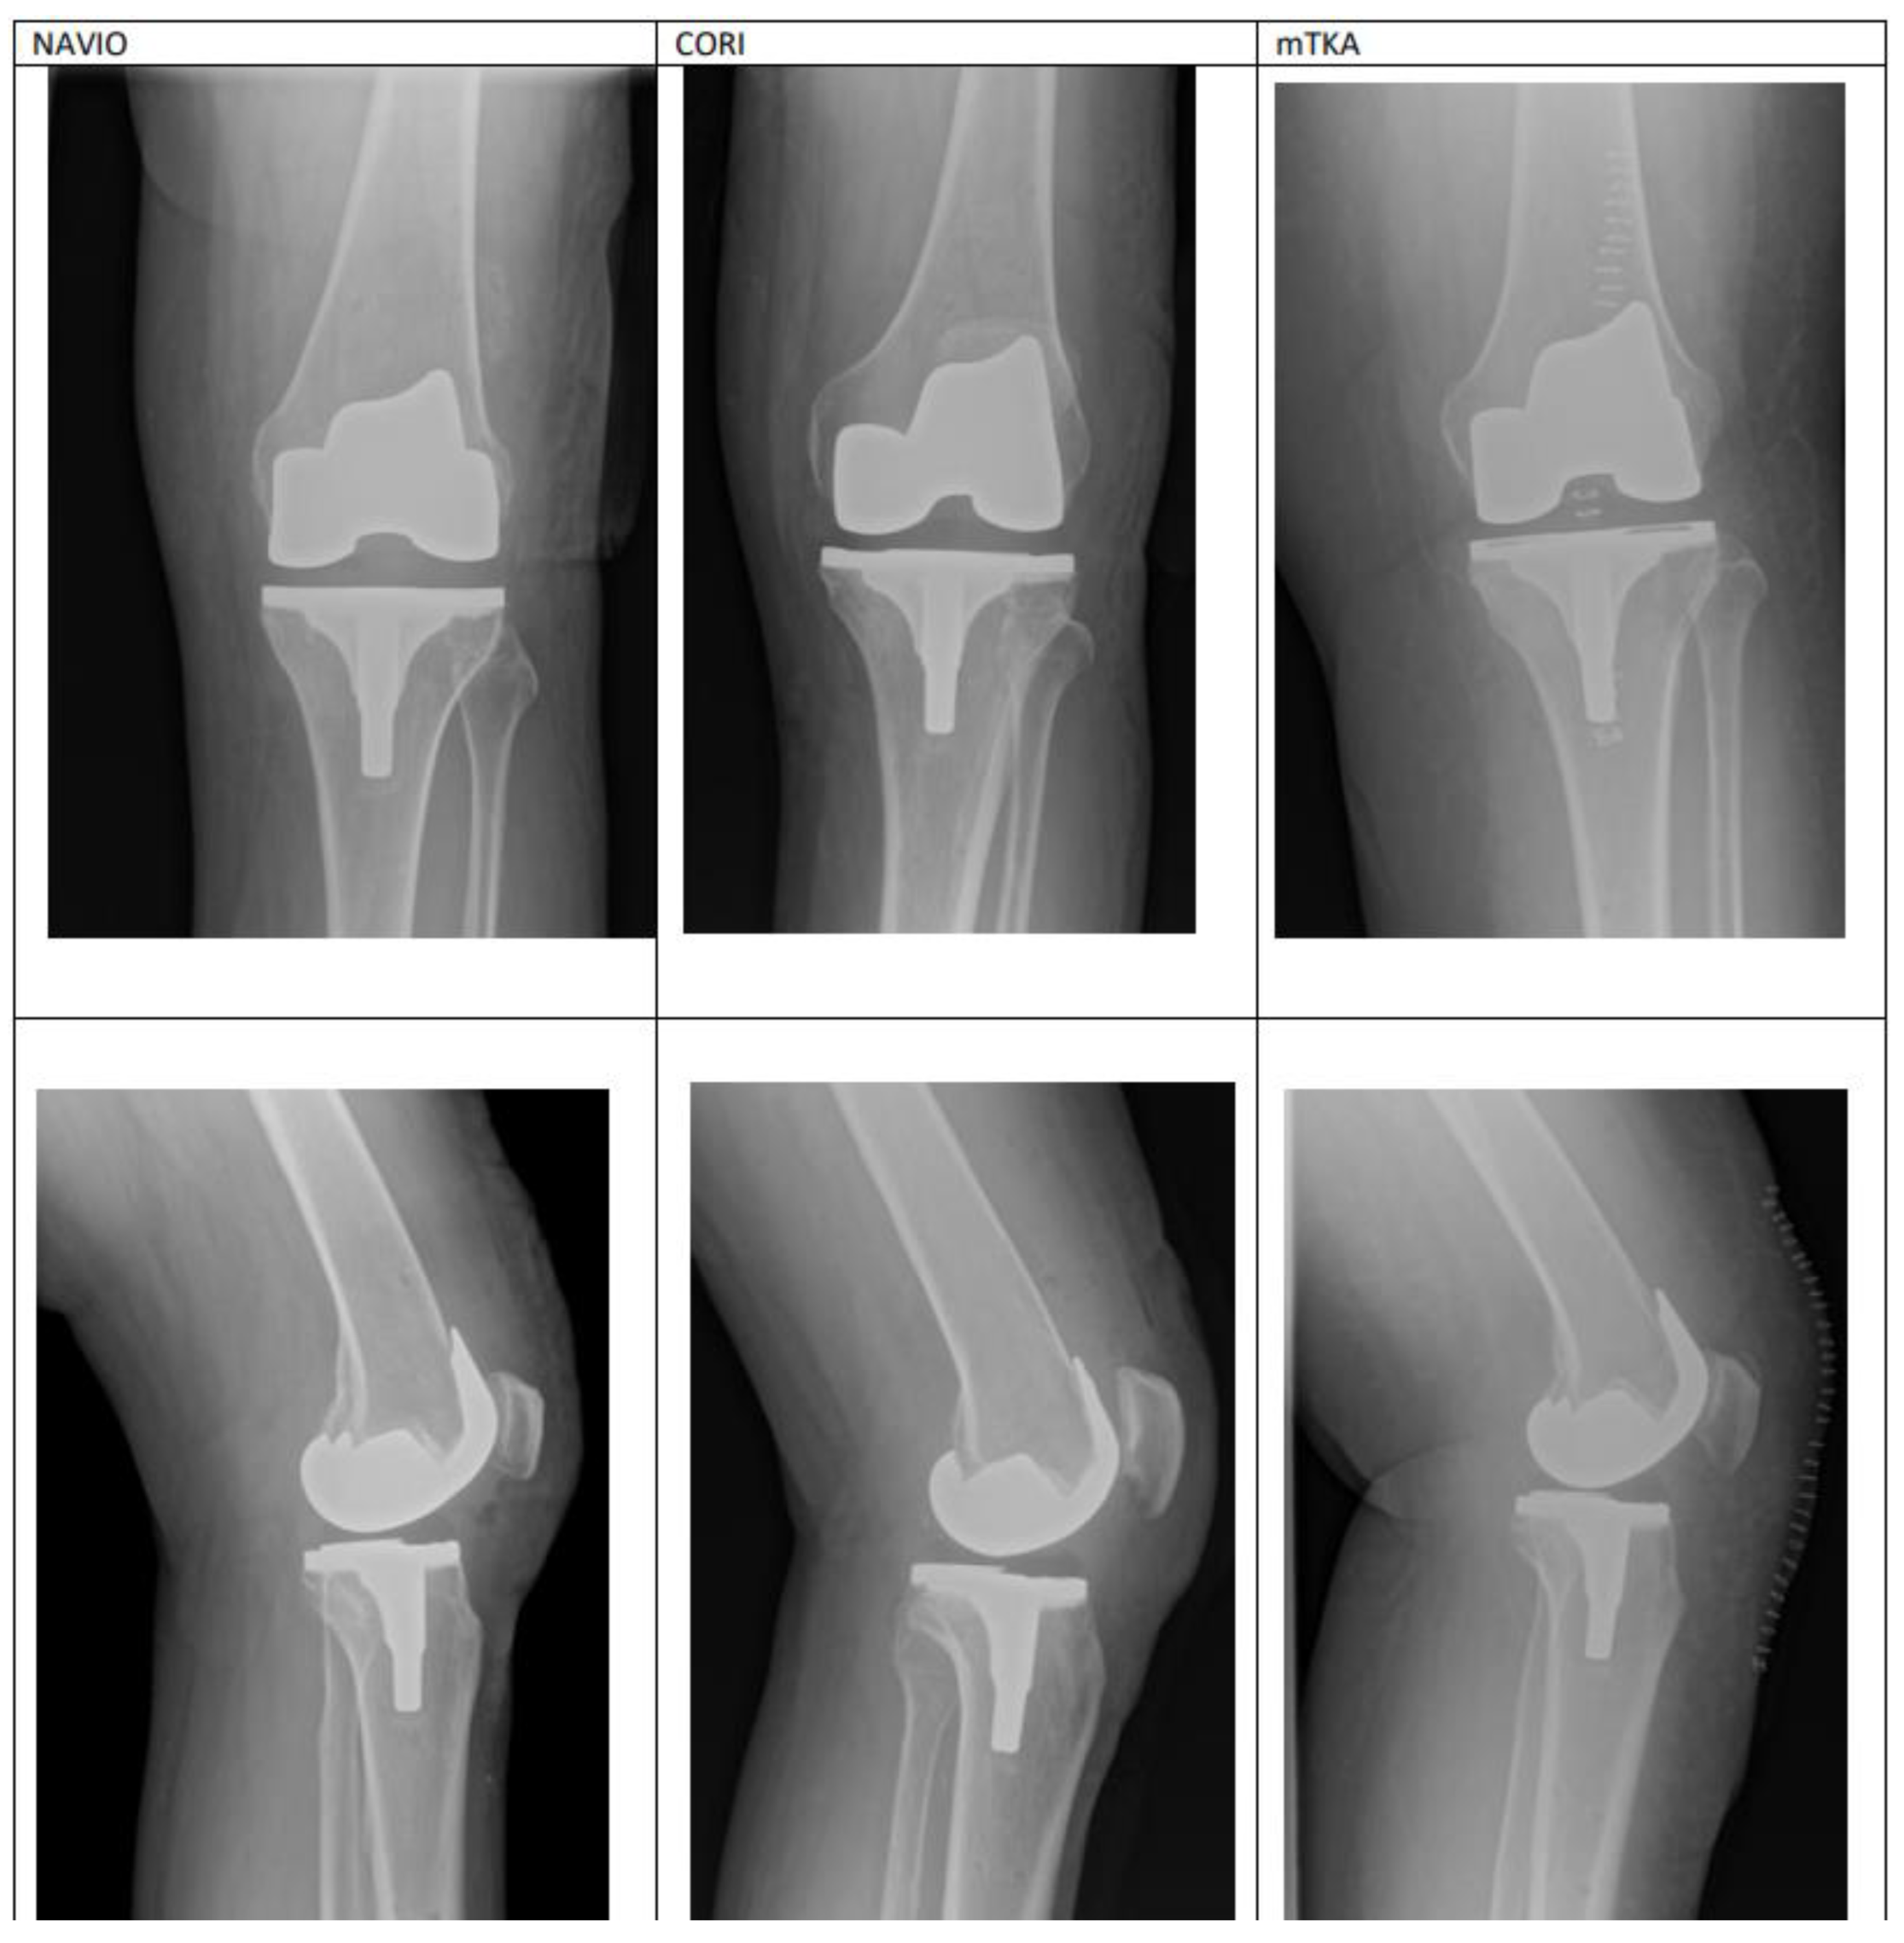

3.3. Radiographic Evaluation of Femoral Component Rotational Alignment Postoperatively

| Femoral Component Rotational Alignment | Postoperative results | 1.48 ± 1.117 | 1.33 ± 1.012 | 3.15 ± 1.2163 | 0.0013 |

| Femoral component rotational alignment | - | 1.48 ± 1.117 | 0.0006 | |

| Femoral component rotational alignment | - | 1.33 ± 1.012 | 0.0127 | |

| Femoral component rotational alignment | - | 3.15 ± 1.2163 | 0.0048 |